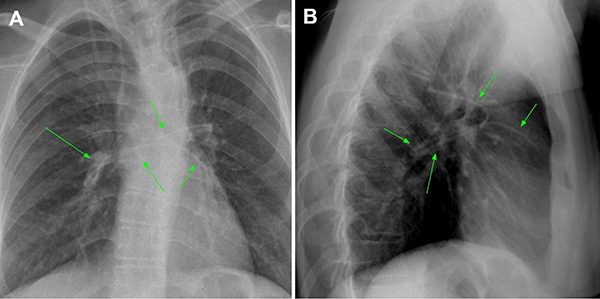

Tras 2 meses, la paciente volvió a consultar en guardia por náuseas, cefalea bifrontal con irradiación holocraneana de intensidad moderada y vómitos. Al examen físico se constató limitación de la mirada superior y colección líquida sobre herida craneal de derivación. Se realizó TC de cerebro con evidencia de ventriculomegalia y desconexión de catéter distal a la válvula (Figura 1). El estudio radiográfico reveló migración caudal del segmento distal del catéter al corazón (Figura 2). El segmento migrado fue rescatado mediante un abordaje endovascular transfemoral, en el cual se enroscó el catéter migrado con un catéter pigtail y se lo desplazó hasta la vena ilíaca primitiva izquierda para luego ser capturado a nivel ilíaco con un lazo trilobulado (Figura 3).

Figura 1. A y B. Corte axial y sagital de TC de cerebro evidenciando marcada hidrocefalia supratentorial. C. Reconstrucción 3D de dicha tomografía, se observa desconexión del catéter distal (flecha verde). Aclaración: sobre mastoides izquierda se evidencia catéter calcificado de válvula previa abandonada. D. Imagen intraquirúrgica con evidencia de desconexión de segmento distal.

Figura 2. A y B. Radiografías de frente y perfil respectivamente realizadas previo a la intervención endovascular en donde se evidencia migración del catéter distal a la cavidad cardíaca (flechas verdes).